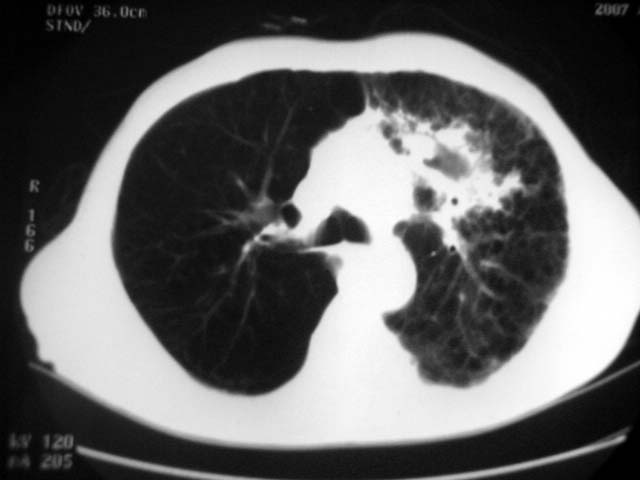

以下是引用zjzjr在2007-9-4 17:00:00的发言:[br]双上肺继发型结核伴左上肺空洞形成.慢性支气管炎伴肺气肿.

以下是引用liuzheng_9326在2007-9-4 16:23:00的发言:[br]痰检未见结核菌, 治疗后症状好转。图像符合陈旧性结核伴感染。